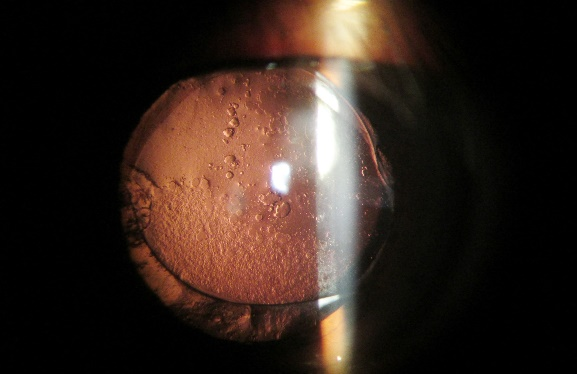

5、后部反光照明法

后部反光照明法的光焦点与显微镜焦点不在同一平面上,是借后部反射回来的光线检查角膜和晶状体上透明的、半透明的正常和病理组织。

如用于观察巨细胞病毒性角膜内皮炎的钱币状KP、后部多形性角膜营养不良(polymorphous posterior corneal dystrophy,PPCD)的轨道征以及格子样角膜营养不良的特征性病变。

巨细胞病毒性角膜内皮炎的钱币状KP